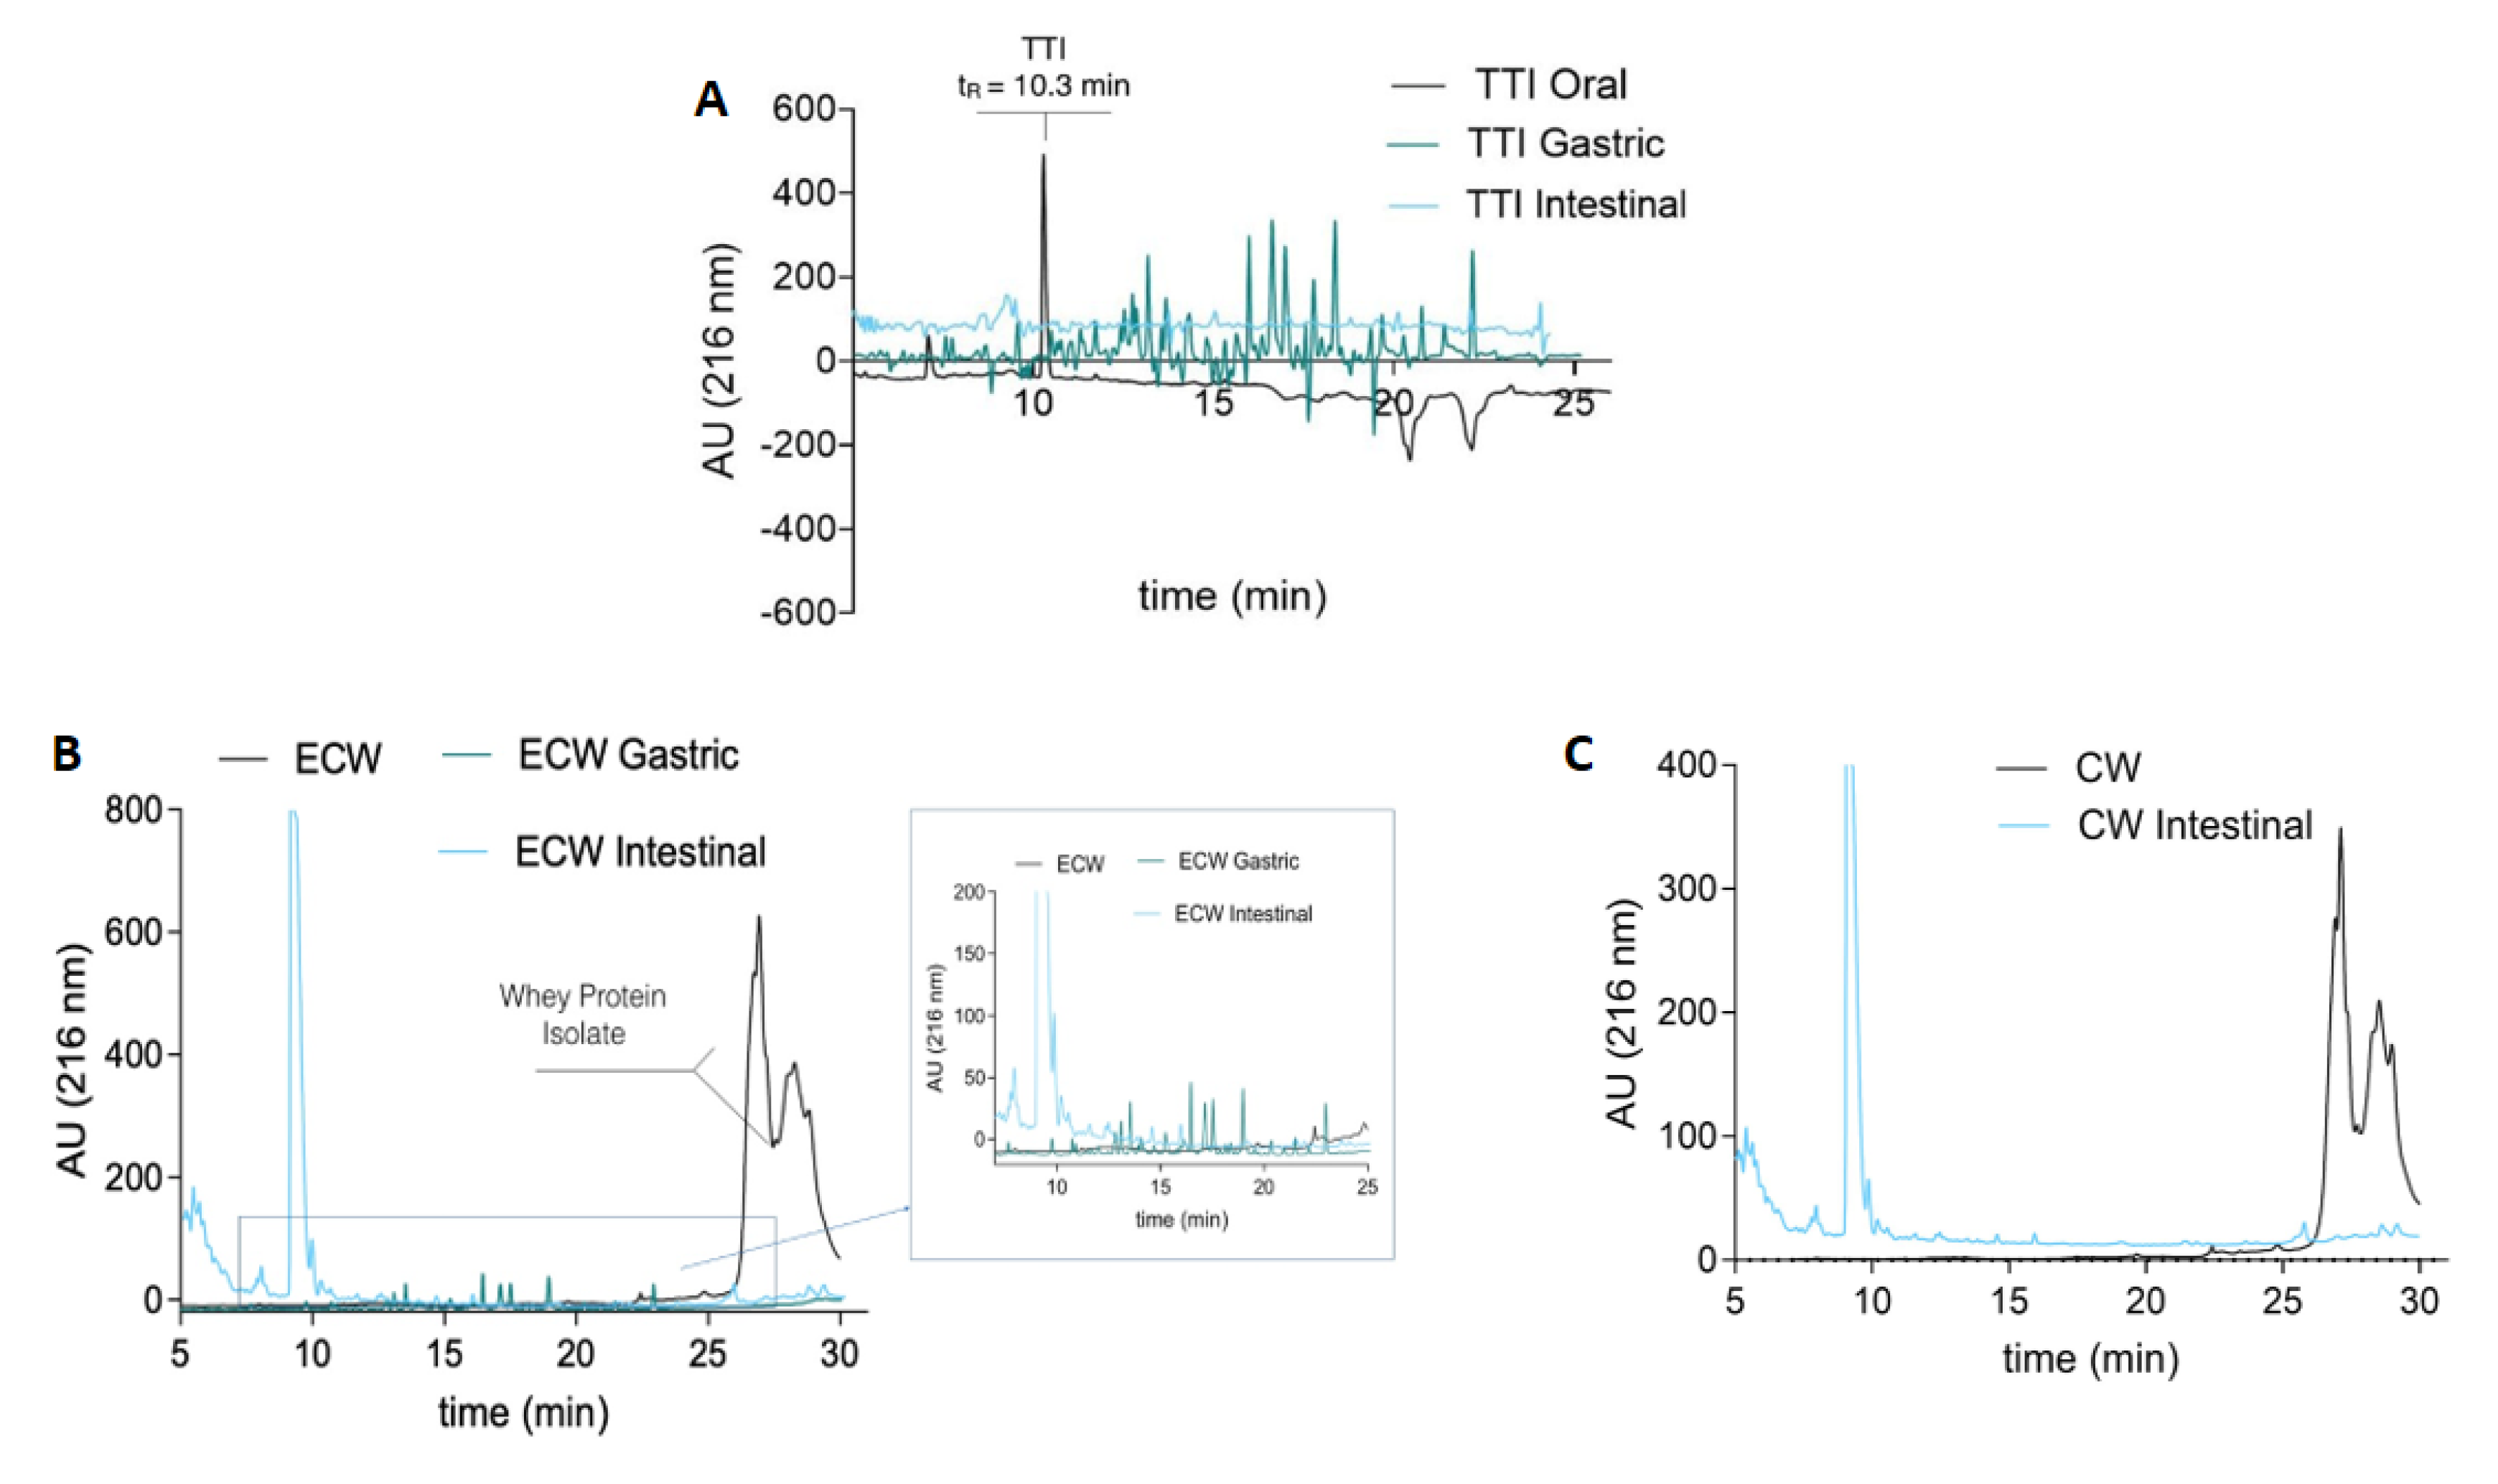

3.4. In Vitro Stability in Simulated Physiological Conditions of the Gastrointestinal Tract